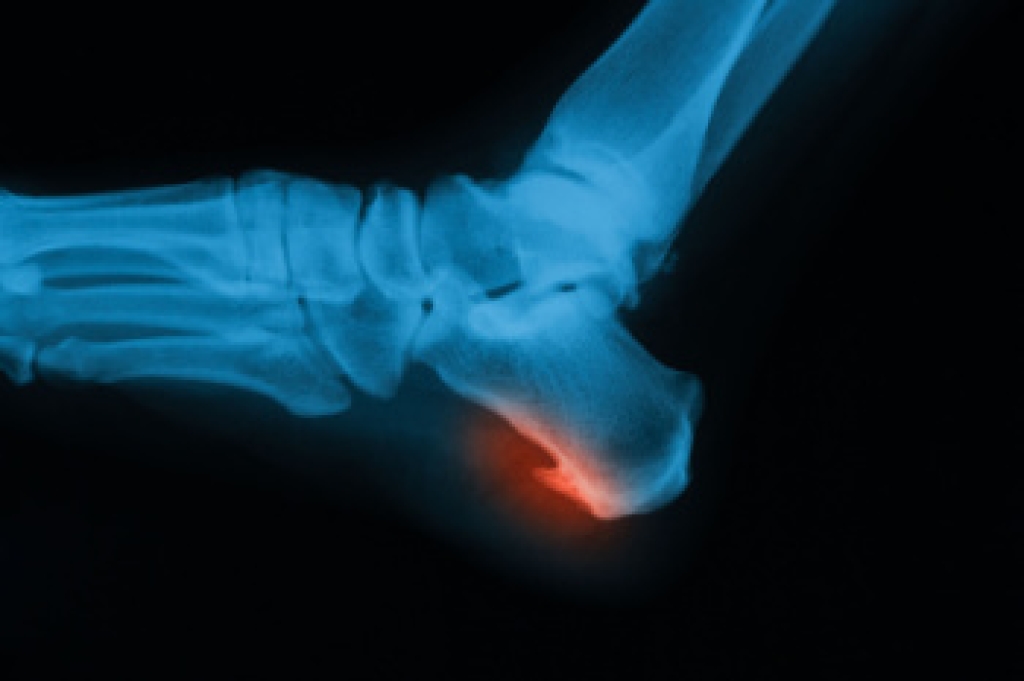

Stretching the muscles in the foot is an important part in any physical activity. Feet that are tight can lead to less flexibility and make you more prone to injury. One of the most common forms of foot pain, plantar fasciitis, can be stretched out to help ease the pain. Stretching can not only ease pain from plantar fasciitis but also prevent it as well. However, it is important to see a podiatrist first if stretching is right for you. Podiatrists can also recommend other ways to stretch your feet. Once you know whether stretching is right for you, here are some excellent stretches you can do.